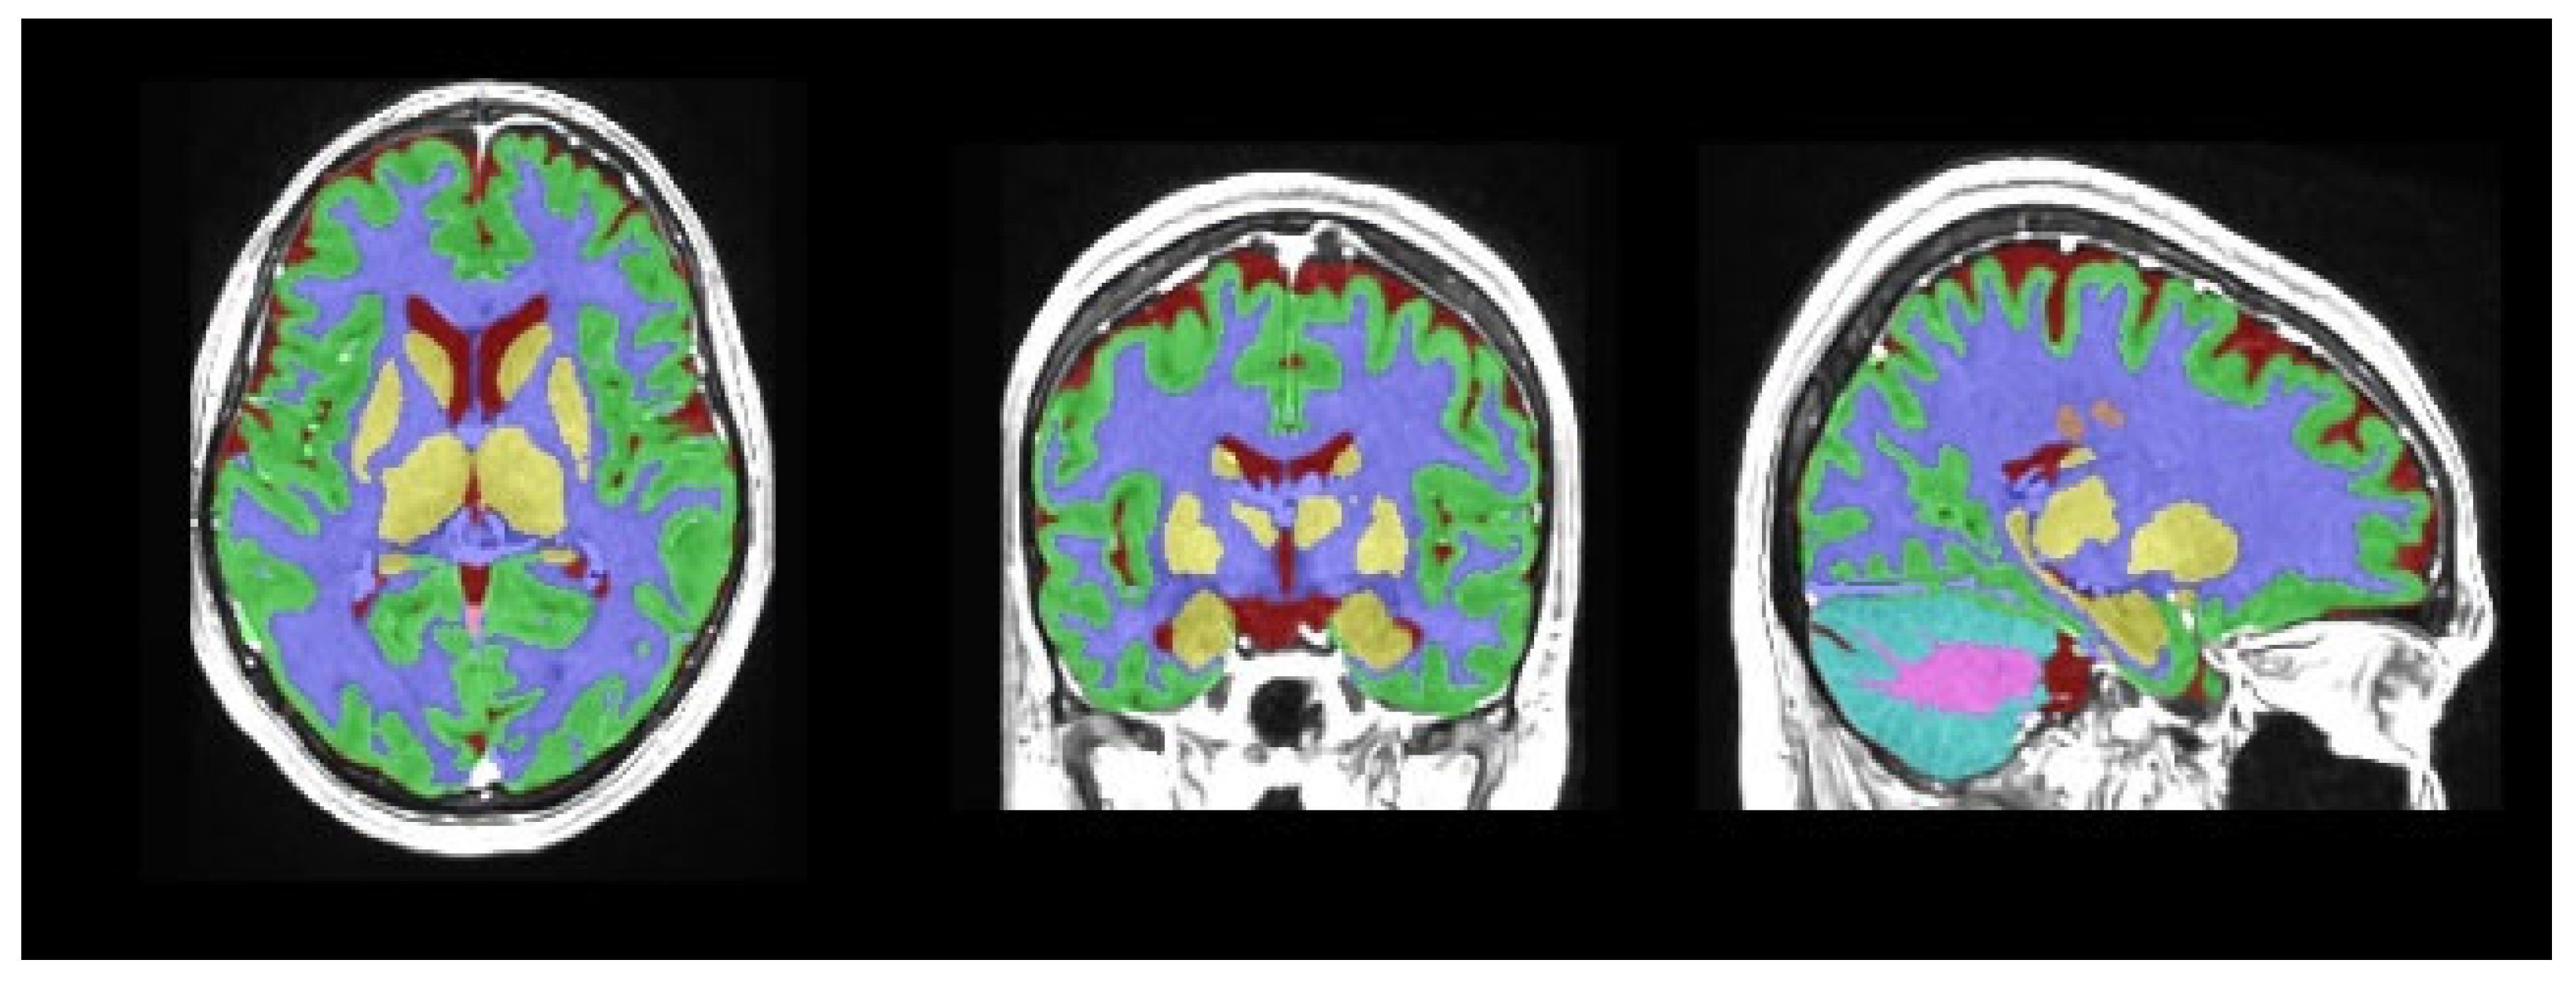

- Manjón, J.V.; Coupé, P. volBrain: An Online MRI Brain Volumetry System. Front. Neuroinform. 2016, 10, 30. [Google Scholar] [CrossRef]